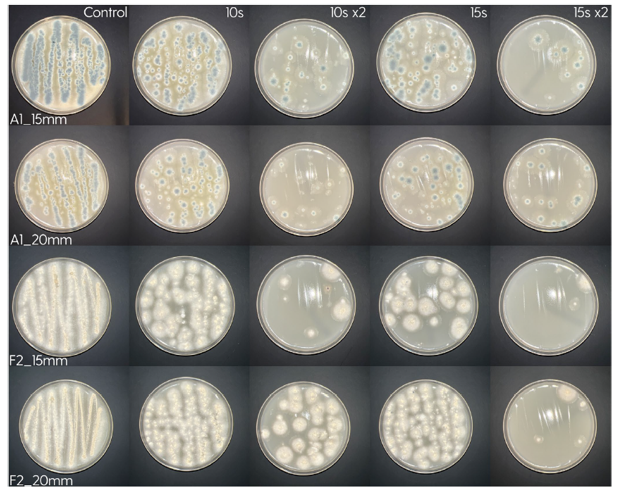

Treatment of the Petri plates inoculated with live bacteria using Ocu-Vet UV-C for 15 seconds at a 10 mm distance.

Photos of the Petri plates, 72 hours after bacterial (Pseudomonas aeruginosa) inoculation.

Image (A) shows positive bacterial growth inhibition (full translucency) at the treatment site after one dose of

UV-C for 15 seconds at 10 mm distance.

Image (B) is the control plate. The blue lines divide the plate into quadrants.

Photos of the Petri plates, 72 hours after bacterial inoculation. Both plates show complete (positive) bacterial growth inhibition (full translucency) at the treatment site after two UV-C doses of 15 seconds at a 15 mm distance. The blue lines divide the plate into quadrants.